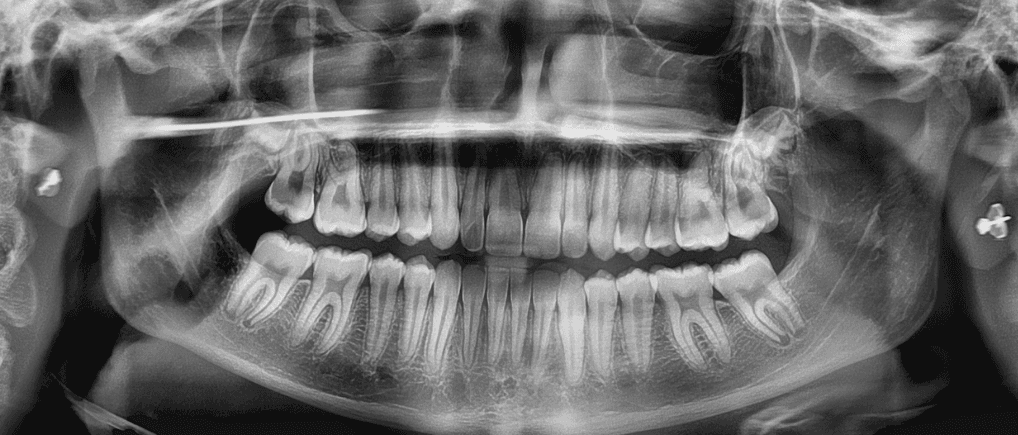

Female, 14 | Treatment time: 21 months

Diganosis: Lower anterior crowding, mild maxillary spacing, misalignment of anterior teeth, rotated premolars and molars

X-RAYS